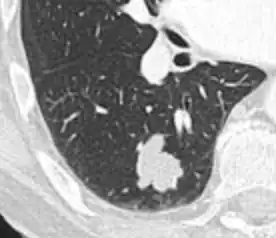

- In case of calcifications, a popcorn-like appearance indicates a hamartoma, which is benign.[3]